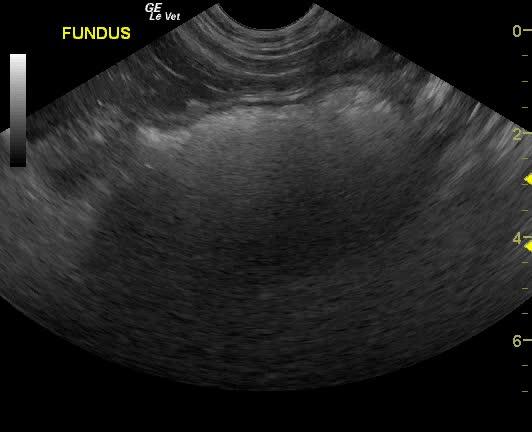

The gastrointestinal tract in this patient presented a 6+ cm hair accumulation in the fundus. The pylorus was free of evident pathology. The remainder of the intestinal tract was structurally unremarkable.

Trichobezoar